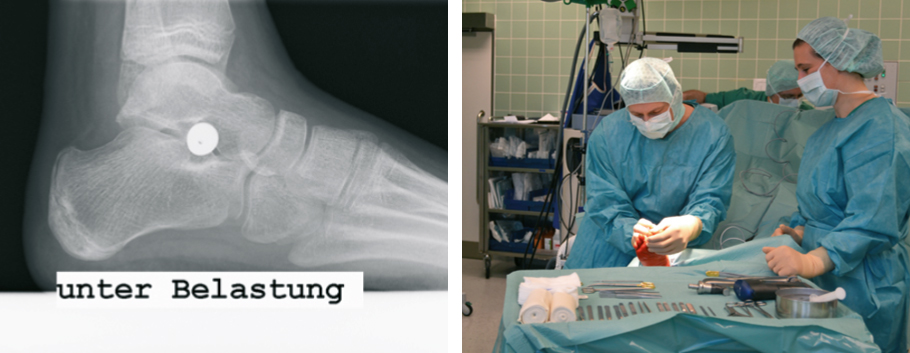

For this a modern minimum invasive Procedure, the so-called arthroereisis is available for some years. Through a small incision of no more than 2 cm, a special invented screw is inserted into the lower ankle. Important soft tissues or joints wont be stiffened or destroyed.

Flatfoot raising comes by the the screw. After two weeks a normal ist load possible. The Screw can be removed after 2-3 Years, the improved foot positions remains.